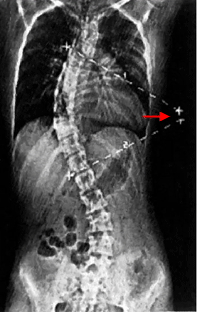

على اليمين صورة أشعة سينية X-Ray تبين كيفية حساب درجة زاوية إنحناء الجنف (زاوية كوب Cobb Angle) , الزاوية b هي زاوية الإنحناء و تساوي الزاوية a , و تساوي 70 درجة. على اليسار صورة لأشعة مقطعية محوسبية (بالحاسوب) Computerized Tomographic Scan CT و حساب الزاوية بالكمبيوتر.

و كذلك بالأشعة يمكن معرفة ما إذا كان الجنف (الإنحناء) بنيوي أو مُعاوض (تعويضي) Compensatory Curvature , الإنحناء المُعاوض يحدث نتيجة للإنحناء البنيوي ليتوازن الجسم. تُأخذ صورة أشعة للشخص و هو منحني جانبياً لليمين و أخرى و هو منحني جانبياً لليسار, مما يؤدي إلى إختفاء الإنحناء المُعاوض و لكن الإنحناء البنيوي يظل. و هذه الطريقة كذلك تفيد في معرفة مرونة العمود الفقري لدى المريض.

في الصورة, في حال الوقوف الجنف يكون صدري قطني أيسر, عند الإنحناء يساراً لا يختفي الإنحناء الصدري لأنه بنيوي , و لكن عند الإنحناء يميناً يختفي الإنحناء القطني مما يعني بأنه مُعاوض و ليس بنيوي.

الفقرات باللون الأحمر = الفقرات الصدرية و الفقرات باللون الأصفر= الفقرات القطنية.